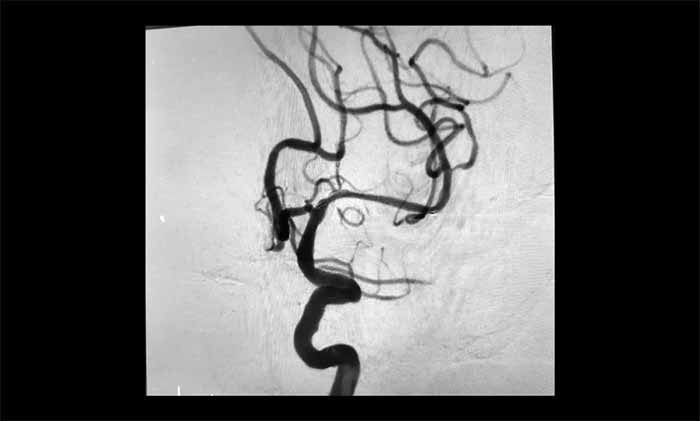

席刚明教授、王贵平博士团队经过全面评估,最终在全麻下精细操作,利用微导丝穿过闭塞段,并以“球囊扩张+支架置入”完成血管再通,为患者打通这条关键的“生命线”。术后患者血流通畅,恢复良好。

近年来,该团队利用神经介入技术,已成功为众多患者开通闭塞的颈动脉、椎动脉和大脑中动脉,帮助他们重获健康生活。

▲ 左侧大脑中动脉顺利开通